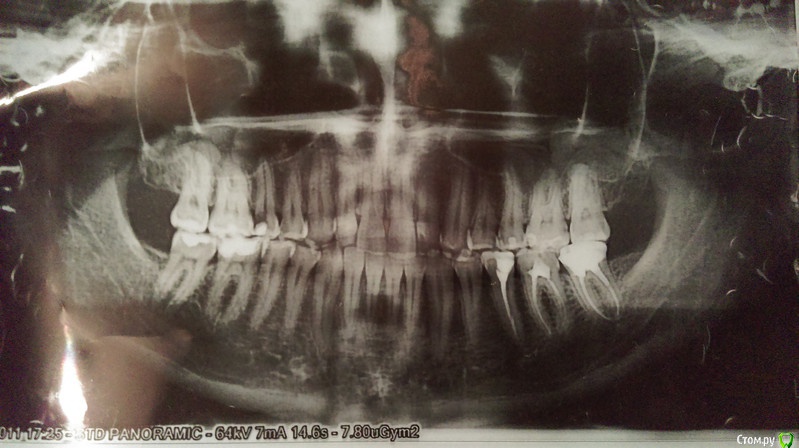

Bizzzin Опубликовано 7 декабря, 2015 Поделиться Опубликовано 7 декабря, 2015 (изменено) Добрый день! У меня частично оголились шейки клыков и одного близлежащего к каждому из них зуба. По виду напоминает клиновидный дефект. Стоматолог-ортопед поставил мне диагноз пародонтит. При этом сказал, что оголение шеек указанных зубов произошло из-за неправильного прикуса (хотя когда сжимаю зубы - нагрузки на клыки не чувствую). Его план лечения включает в себя изменение прикуса, а именно, увеличение нагрузки на жевательные зубы путем установления на них коронок (по одной) и замены пломб.По его словам, указанное лечение сможет замедлить этот патологический процесс. Пока что завершаем первую коронку. Из предварительных обследований помимо снимка (приложение), делал слепок челюсти (т.е. когда вставляют в ротовую полость штуковину с синим подобием пластилина, который постепенно застывает). Пока не слишком поздно, хочется узнать мнение других специалистов в этой области - адекватно ли подобран способ лечения?Могли ли оголиться шейки клыков в результате неправильного прикуса, в то время как непосредственно на них давления вроде как не оказывается?Если необходимость в изменении прикуса действительно существует, насколько позволительно это делать "на глаз"? Делались только предварительные обследования, указанные выше. Спасибо! p.s. Аналогичную тему создал в разделе "Протезирование", но к сожалению, какой-либо информации получить не удалось, из-за чего решил разместить ее также здесь. Прошу уважаемых администраторов проявить понимание. Изменено 7 декабря, 2015 пользователем Bizzzin Ссылка на комментарий